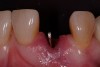

A 54-year-old, non-smoking woman presented with a root fracture at the maxillary right lateral incisor (Figure 1). The patient presented with a 10-mm pocket at the mid-facial probing depth, and a Grade 2 mobility. The preoperative peri-apical digital radiograph can be seen in Figure 2. A natural diastema existed on the distal aspect of the right maxillary incisor, and the patient did not wish to have this corrected. To hold the natural tissue emergence profiles throughout the treatment phase, the immediate implant placement and provisionalization procedure was chosen to treat the affected site. Before the procedure, an occlusal index and registration was taken so that when the retrofitting of the natural tooth shell was accomplished, the exact location of the natural tooth shell could be seated on the implant abutment at the time of implant placement (Figure 3). After administration of an appropriate local anesthetic, tooth No. 7 was removed by an atraumatic technique to preserve the natural soft tissue emergence profiles present pre-surgically (Figure 4). After tooth removal, debridement of the extraction socket was accomplished by curettage of the socket, followed by rotary instrumentation with a course #8 round diamond to ensure removal of all remnants of the periodontal ligament, granulation tissue, and localized debris. To aid in the debridement, the patient was started on a preoperative administration of Augmentin 875 mg, taken the day before treatment, and once again 1 hour before the surgical visit. The patient then continued this antibiotic course for a total of 10 days.

Figure 4  Atraumatic tooth removal.

Figure 4